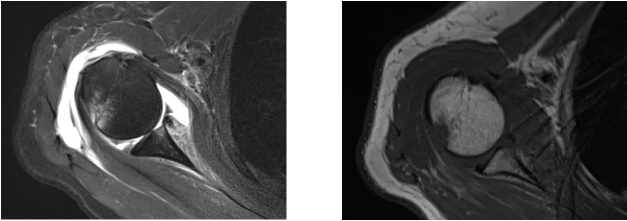

病例2

病史摘要:女性,65歲,跌傷致右肩活動受限9天。

MR圖示:右側(cè)肱骨頭后上部局部明顯凹陷,骨皮質(zhì)欠光整,周圍見片狀壓脂高信號影(箭頭);前盂唇脫離移位;前下盂唇不連,局部骨質(zhì)分離(三角形);肱骨頭向前移位。